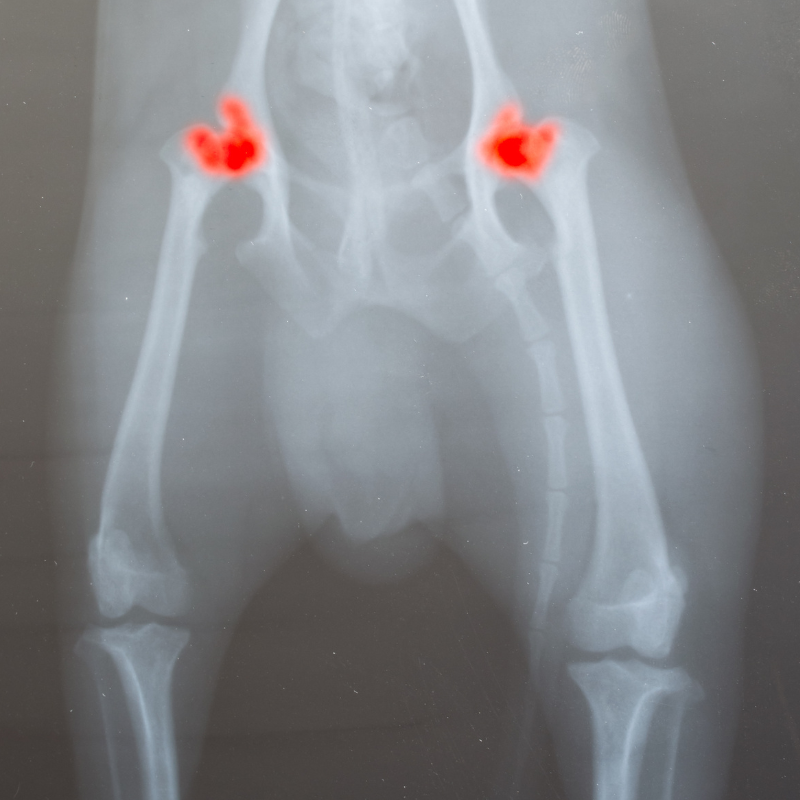

Hüft- & Ellbogendysplasie

Hüft- und Ellbogendysplasie bei Hunden

Der Begriff Dysplasie stammt aus dem Griechischen und bedeutet „schlechte Form“. Hüftdysplasie beim Hund – auch HD abgekürzt – und Ellbogendysplasie - auch ED abgekürzt - ist eine Erkrankung der Hüftgelenke, die zumeist erblich bedingte Ursachen hat und leider ziemlich häufig vorkommt. Aufgrund ihres Körperbaus sind große Hunderassen wie Schäferhunde, Retriever oder Boxer besonders oft von einer Hüftdysplasie betroffen.

Das Ausmaß der Beschwerden einer HD kann bei Hunden je nach Alter und Schweregrad der Hüftgelenksdysplasie unterschiedlich ausfallen. Die Hüftprobleme von betroffenen Hunden können allerdings mit dem Alter stärker werden, falls keine geeignete tierärztliche Diagnose und Behandlung erfolgen.

Eine fortgeschrittene Hüftdysplasie kann bei Hunden sogar zu einer Arthrose an der Hüfte führen.